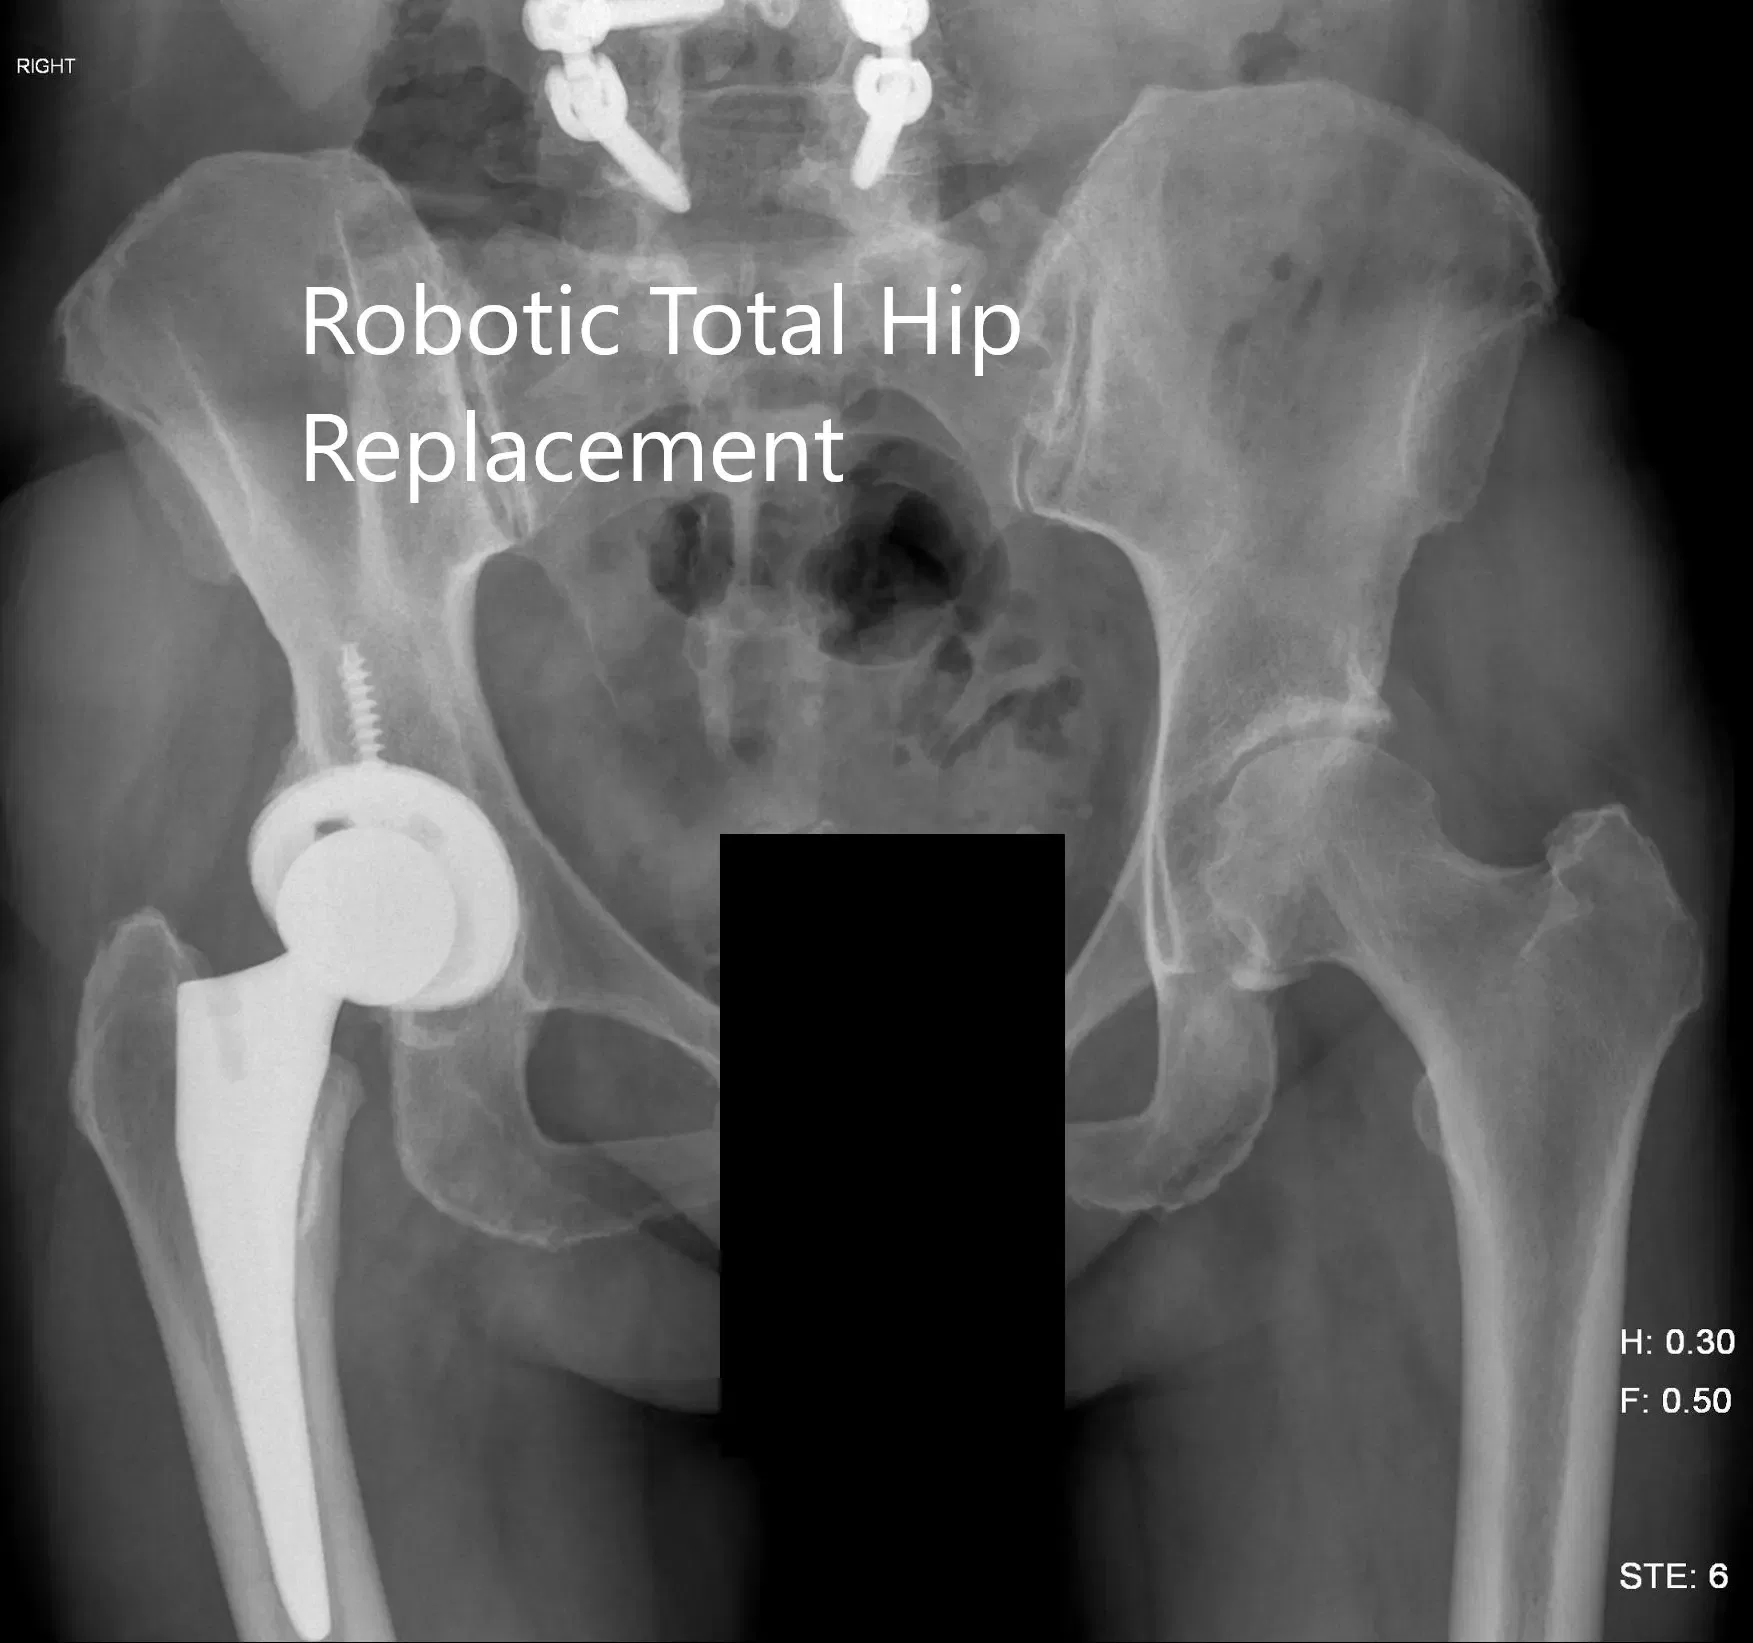

Radiografía preoperatoria que muestra la vista AP de la pelvis con ambas caderas.

Radiografía postoperatoria de la pelvis mostrando vista AP.